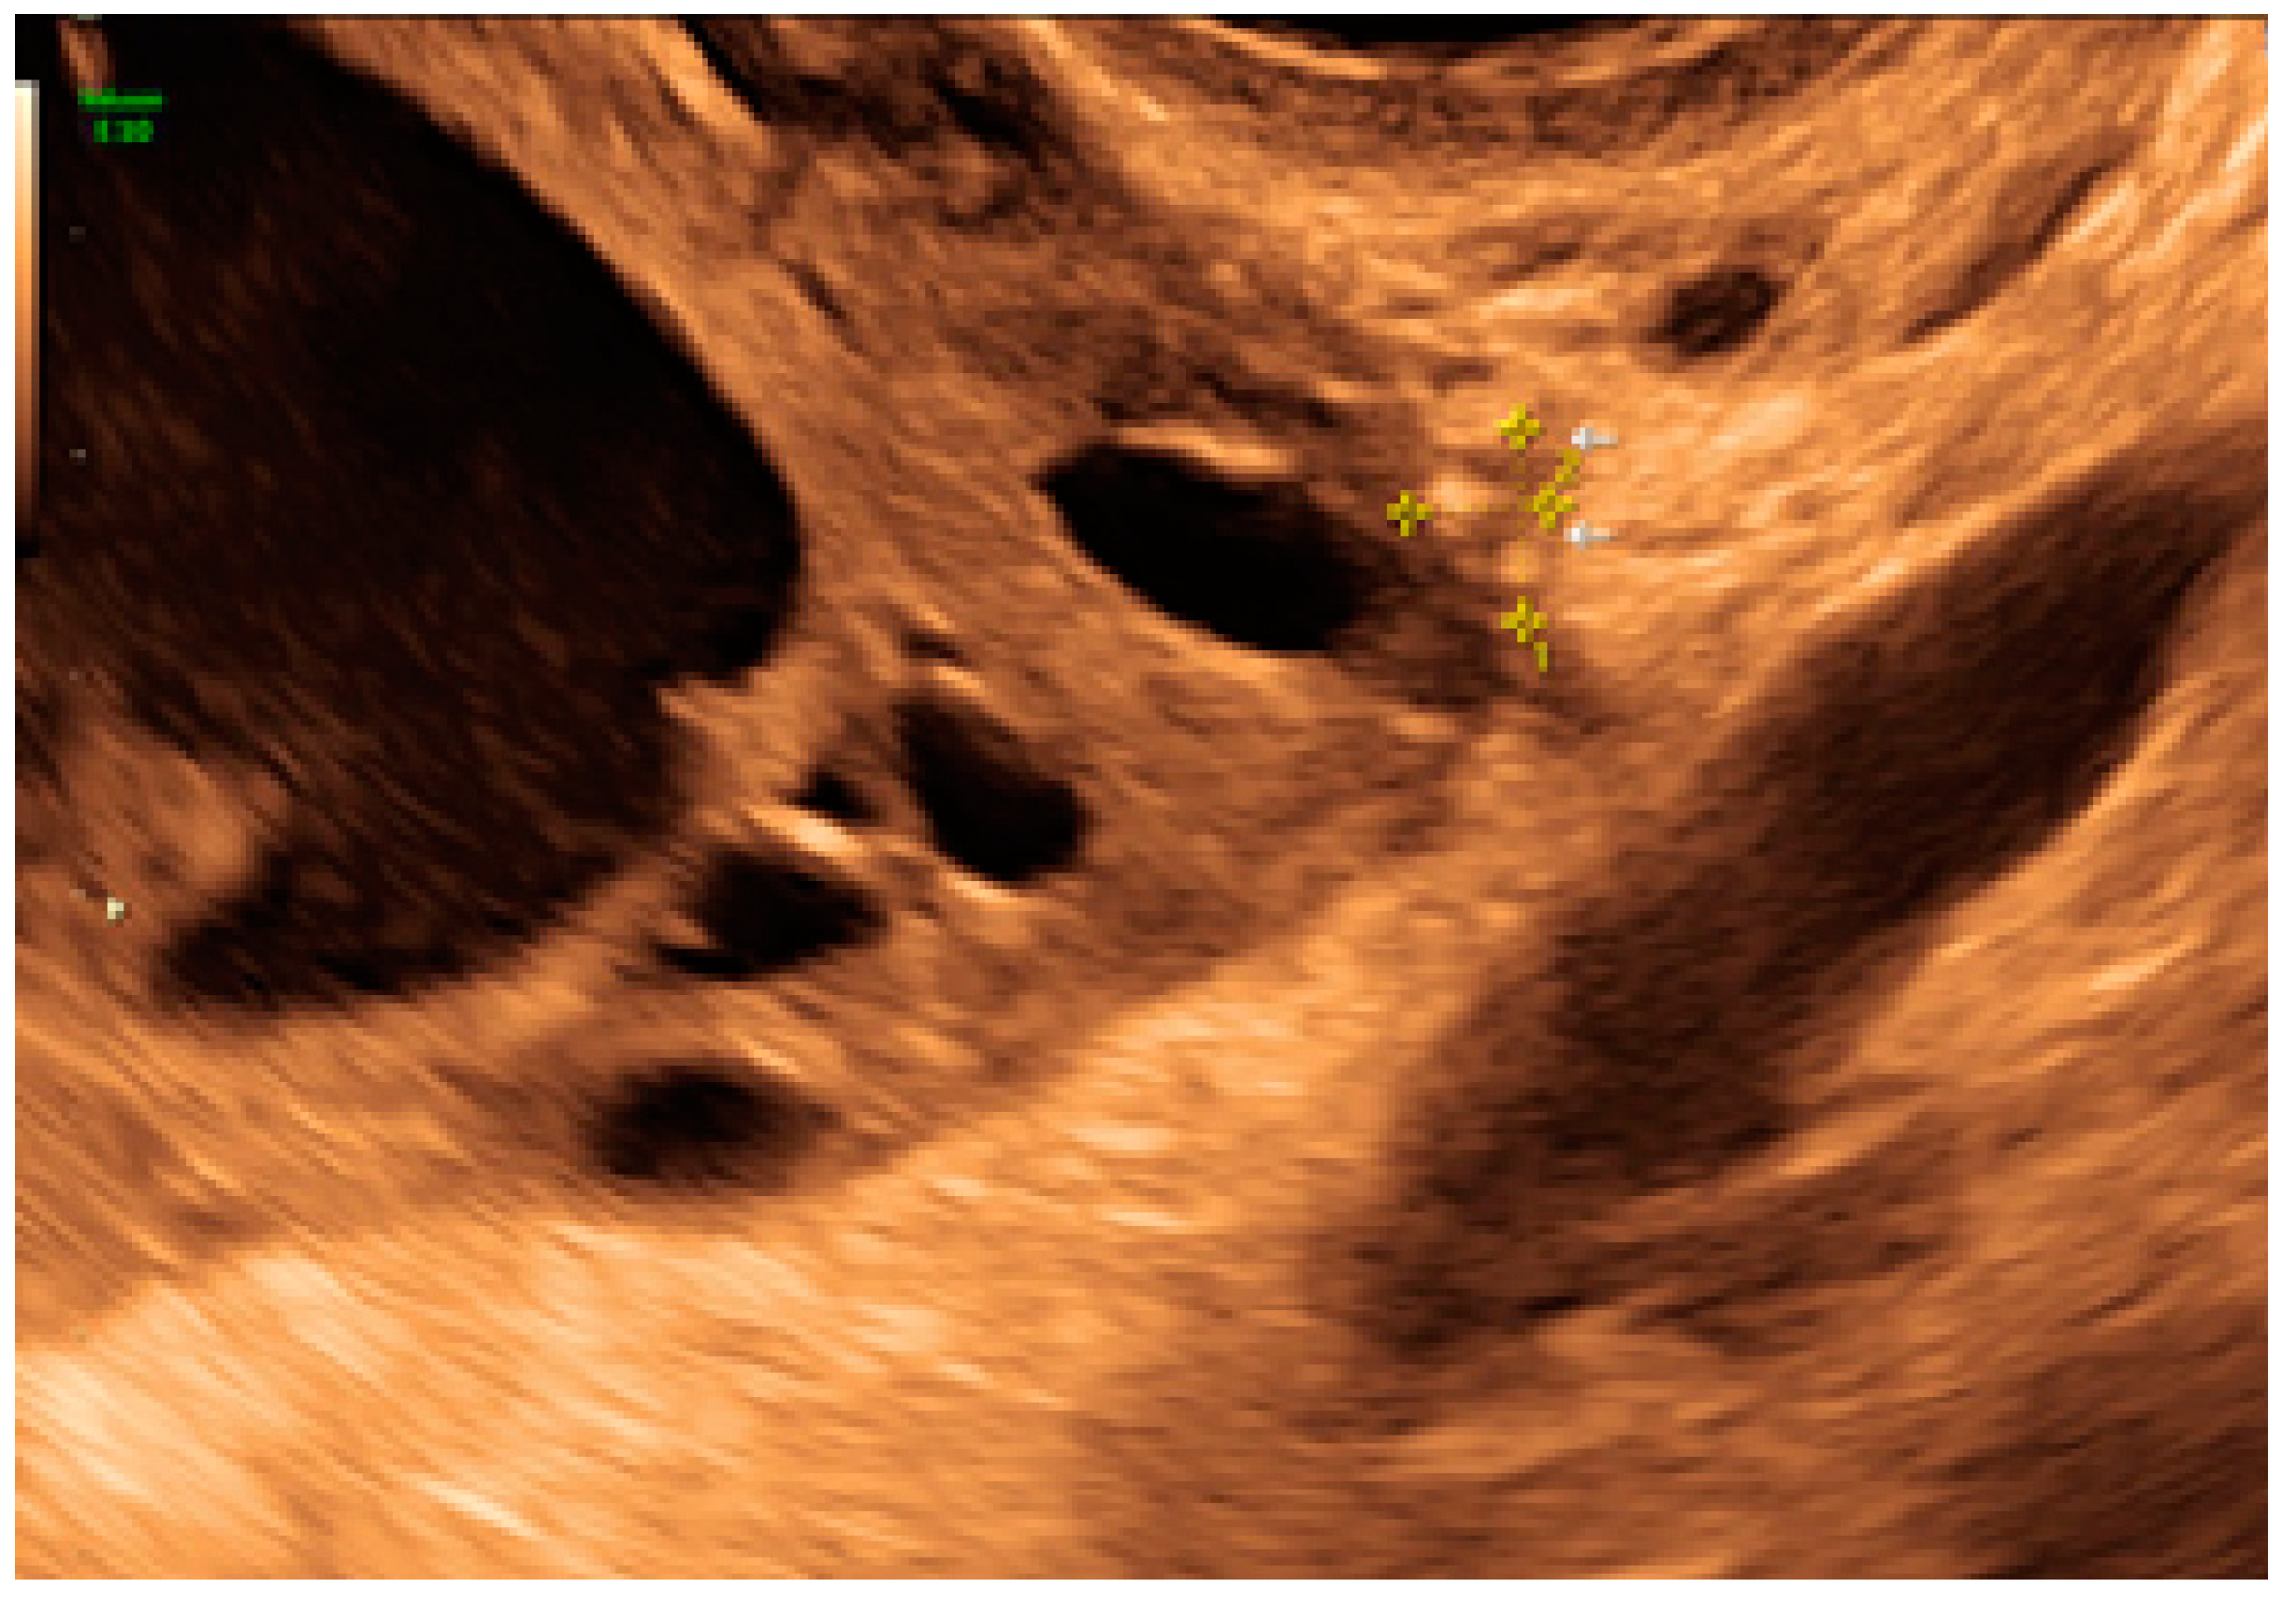

- The lesion may be convex, protruding from the peritoneal surface into the peritoneal cavity (we called this “bulging”), or it may appear as a concave defect in the peritoneum (we called this a “pocket”).

3.2. Cystic Multiple Separate Lesions

3.3. Cystic Lesions Arranged in a Cluster